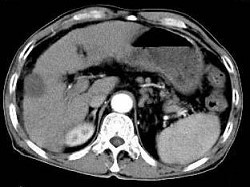

根据所提供的图像,最可能的诊断为()

• A.肝囊肿

• B.肝癌

• C.肝血管瘤

• D.结节性肝硬化

• E.转移癌